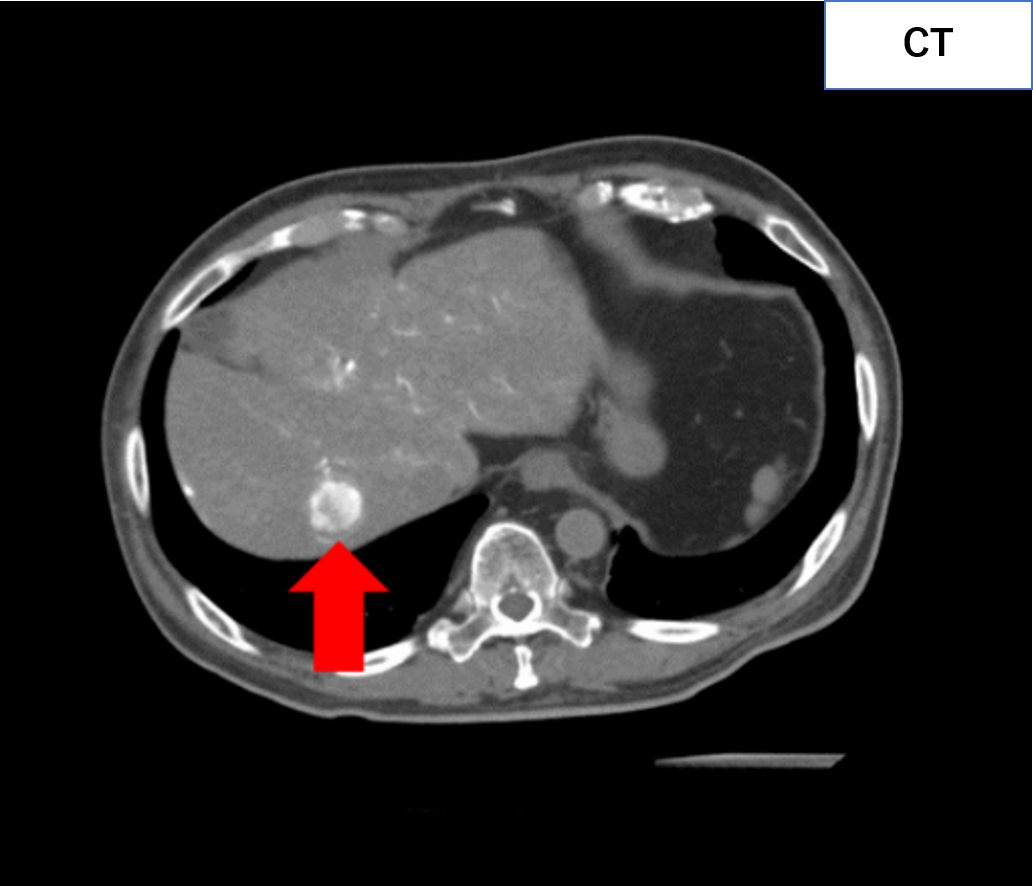

通常のCT画像(下図左)では、正常な組織(臓器や血管など)と病気の「差」が小さく、病気を見つけにくいケースが存在します。静脈から造影剤を注入することで臓器・血管をより明瞭に描出し、病気を見つけやすくすることができます。(下図右の赤矢印)。

単純CTでは見つけられない病気(肝腫瘍)を造影CTで発見!